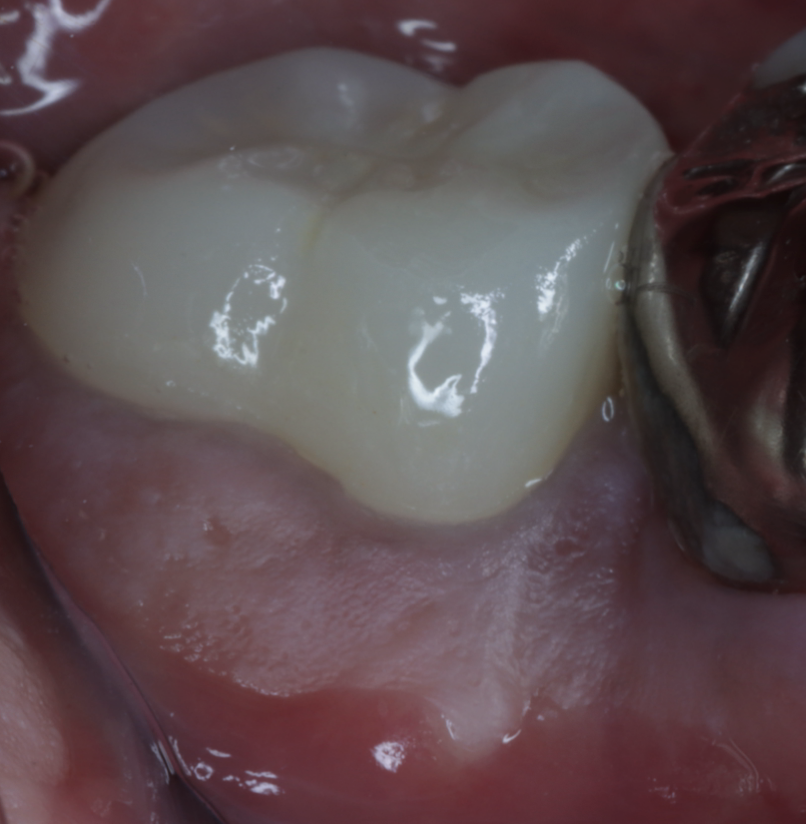

【50代男性】

歯周組織再生療法で歯を残した症例

【歯周組織再生療法】

- 担当医

- 生野 誠

- 主訴

- 奥歯の違和感と歯ぐきの腫れを感じて来院。

他院で「抜歯が必要」と診断されましたが、できる限り歯を残したいという希望で当院にご相談いただきました。

- 期間

- 6ヶ月

- 費用

- 40万円

- 治療内容

- 精密根管治療後、以下の流れで再生療法

・感染組織と不良肉芽を除去

・根面滑沢化(バイオフィルム除去)

・エムドゲイン®+骨補填材による再生誘導

・縫合・閉鎖で再生環境を安定化

- 治療に伴うリスク

- 再感染